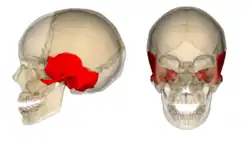

Osso temporal é um osso par que forma as laterais do crânio ou têmporas. É um osso irregular e situa-se ínfero-lateralmente a caixa craniana.

Localização

Situa-se na região lateral e inferior do crânio, constituem as paredes laterais do crânio e na sua cavidade timpânica localizam-se os três ossos da orelha média. A saliência óssea atrás da orelha chama-se processo mastoide. Este osso possui também um processo estiloide, importante para a articulação temporo-mandibular, uma vez que permite a protusão da mandíbula, um côndilo temporal onde se vai "encaixar" o processo condilar da mandíbula e uma cavidade glenoidea.

Imagens

Vista lateral do crânio.

Crânio visto de frente.

Close-up.